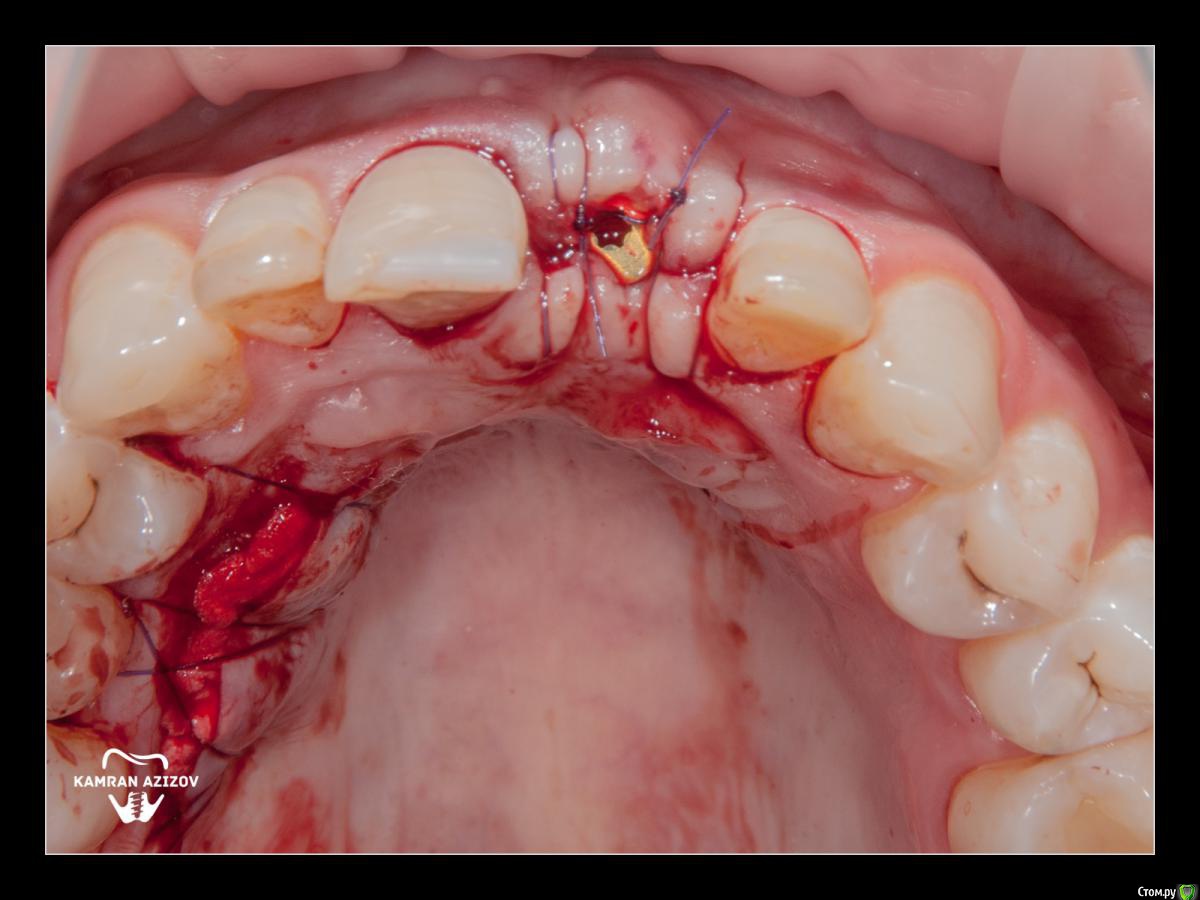

kamranchick Опубликовано 8 октября, 2019 Поделиться Опубликовано 8 октября, 2019 удаление зуба+консервация лунки с вестибулярным ССТчерез 2 месяца имплантация с фдм по карлоссучерез 4 месяца замена на более длинный фдм и широкийпостоянная коронка 5 Ссылка на комментарий